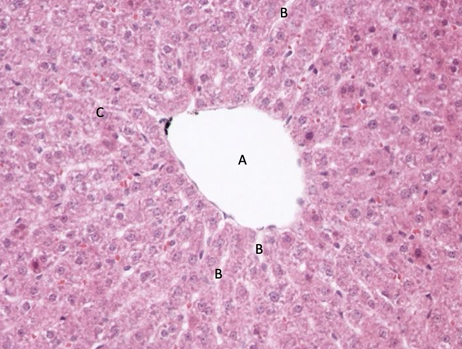

wątroba 407

triada wątrobowa: żyła, tętnica, przewód żółciowy, naczynia limfatyczne

żyła centralna ta wielka dziura

beleczki komórek wątrobowych

naczynia zatokowe

przegroda międzyzrazikowa